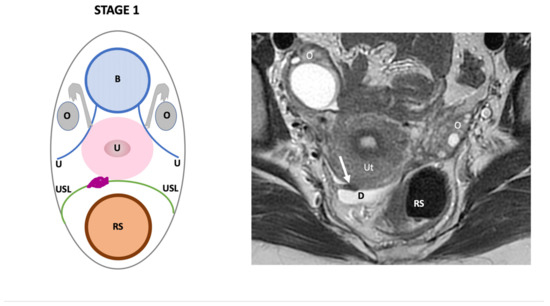

| Endo-Stage MRI | Location | Extent | Risk Stratification |

|---|---|---|---|

| Endo-Stage MRI 0 | Superficial endometriosis |

| Low |

| Endometriosis is strictly confined to the ovaries |

| ||

| Endo-Stage MRI I | Endometriosis is strictly confined to the retrocervical area |

| |

| Endo-Stage MRI II | Endometriosis invades beyond the retrocervical area, but not to the pelvic side-wall |

| Endo-Stage MRI III | Endometriosis extends to the pelvic side-wall and/or causes hydronephrosis or non-functioning kidney |

| Intermediate |

| Endo-Stage MRI IV | Endometriosis has involved the bladder or rectosigmoid colon |

| Endo-Stage MRI V | Multiple deep endometrioticlocations |

| High |